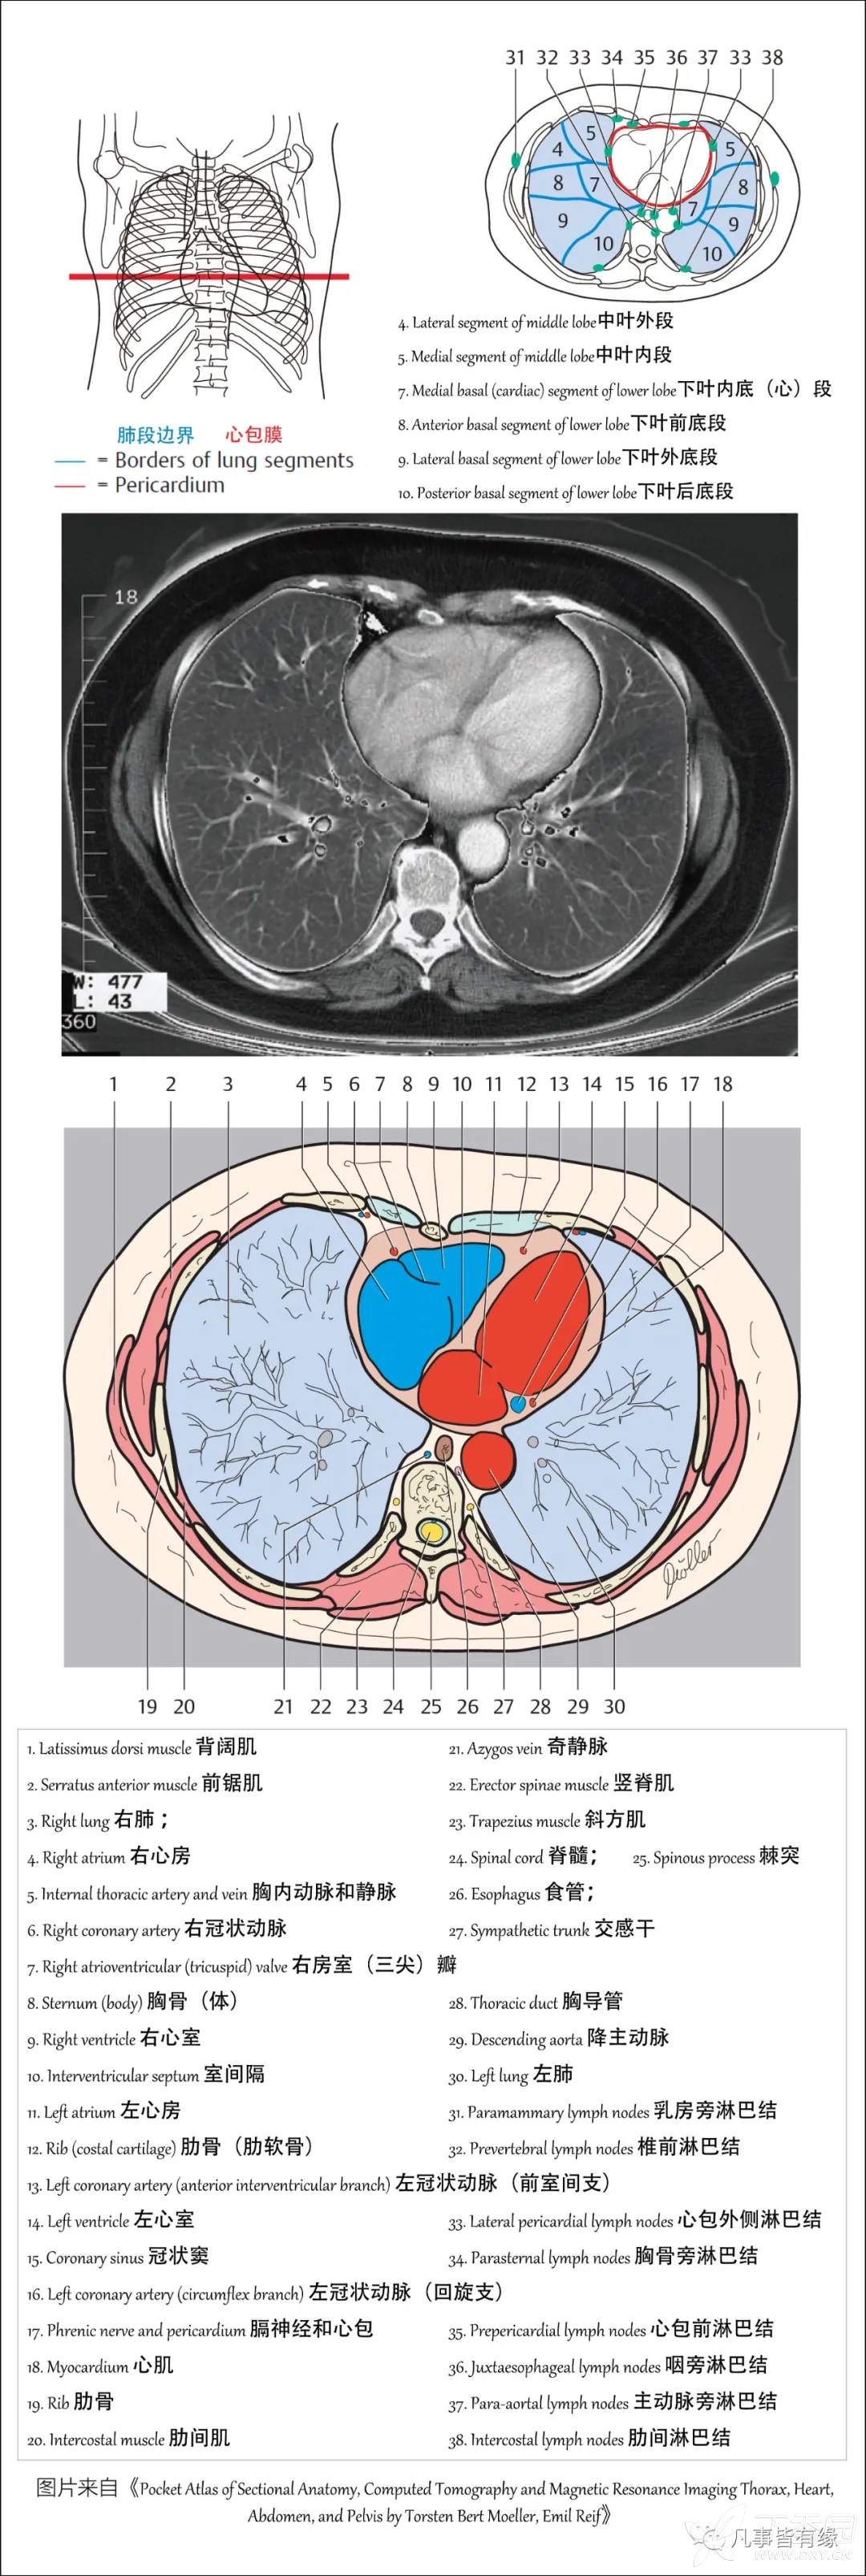

(一)胸部CT轴位断层解剖: